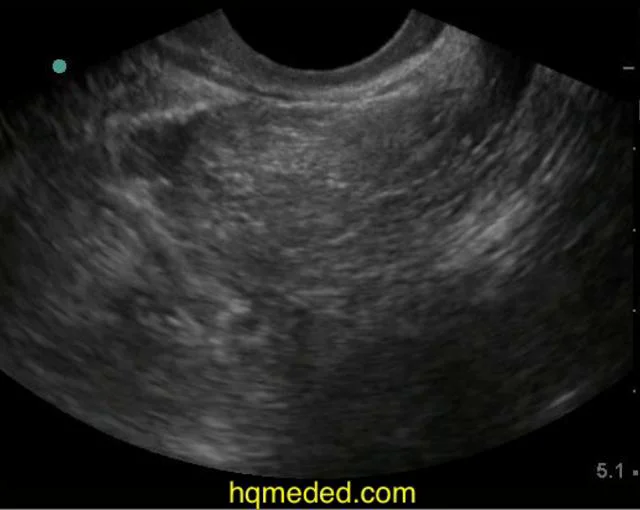

From ultrasound.guide

Pelvic Ultrasound Pelvic Free Fluid Treatment For Free Fluid In Pelvis Treatment for free fluid in the pelvis depends on the cause. Whether or not you have a free fluid in your pelvis can be determined by imaging techniques. Trace free fluid in pelvis. Physiological causes generally resolve without medical intervention. The treatment for free fluid in the pelvis depends on the underlying cause. This is often a normal finding in. Treatment For Free Fluid In Pelvis.